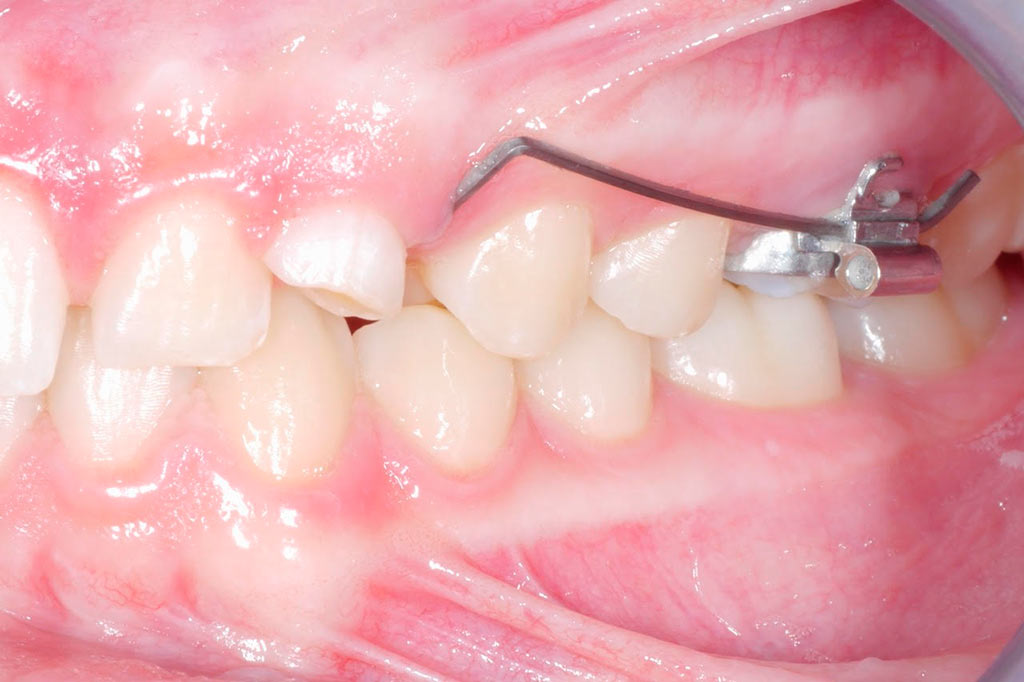

Tracción de canino con k9